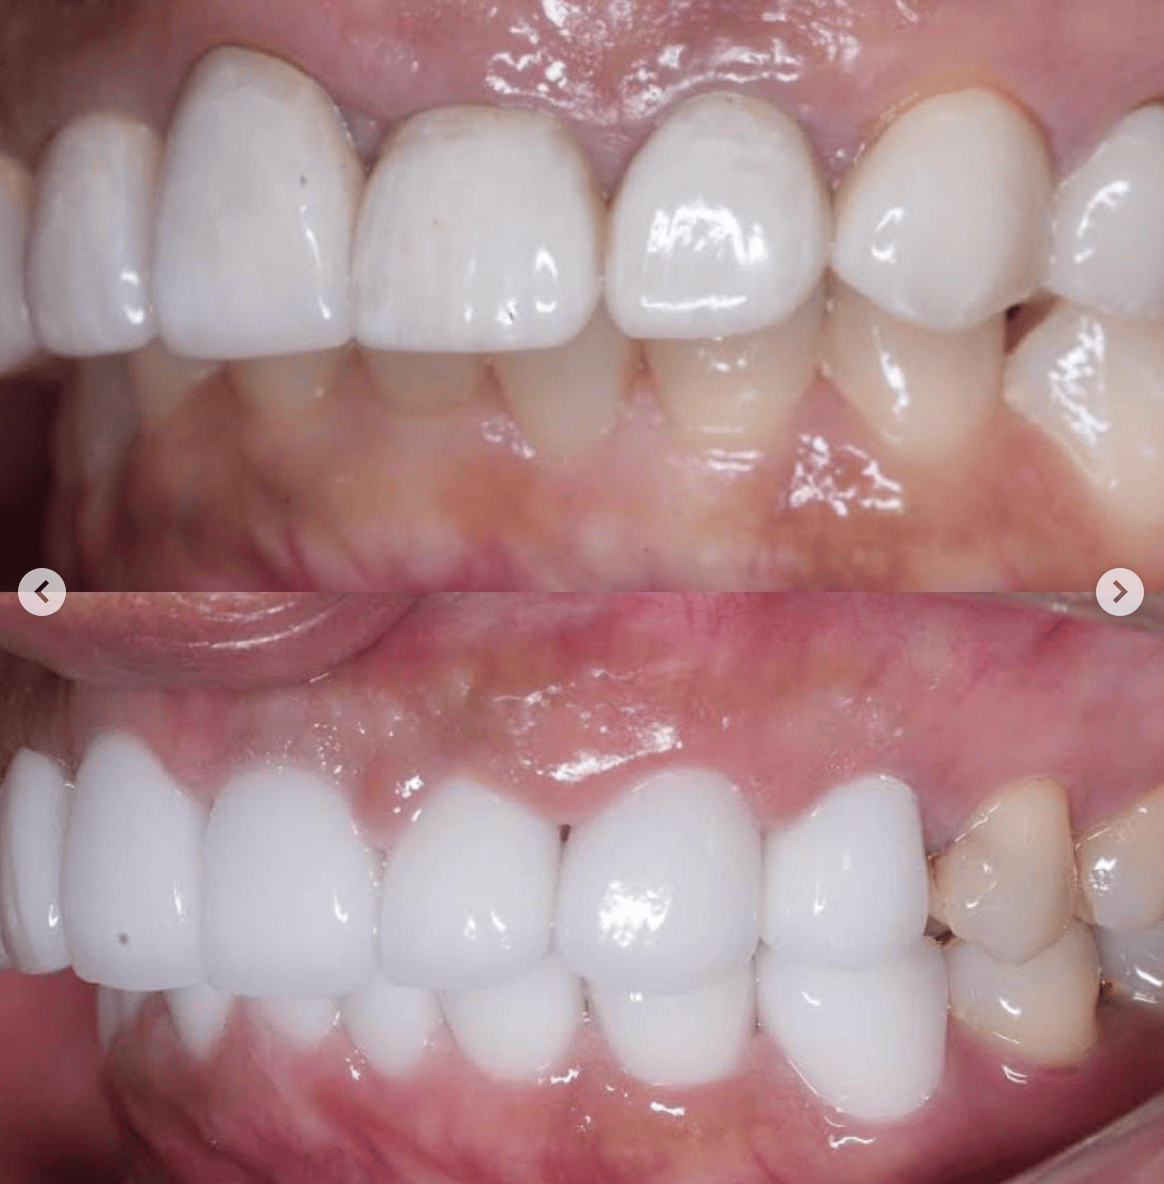

Case032

メジャーリーグでも活躍した元プロ野球選手の山口俊さんのセラミック治療を担当いたしました。

「他院で治療を受けたセラミックが欠けた」というのが主訴でしたが、よく診察するとセラミック欠けただけではなく、被せ物がしっかりと合っていないことが原因で歯茎の腫れがあり、歯石や汚れもつきやすい状態でした。また、歯列も若干歪んでいたので、この機会に全て治療いたしました。

治療後は透明感のある白さで、綺麗な歯並びになりました。また、セラミックをきちんと綺麗に削って適合よくセットしたことにより、歯茎の腫れも改善しました。

セラミックを入れた所の歯茎が腫れていて悩まれてる方はぜひご相談ください。

綺麗に削って適合よくセラミックをしてあげれば必ず改善します。